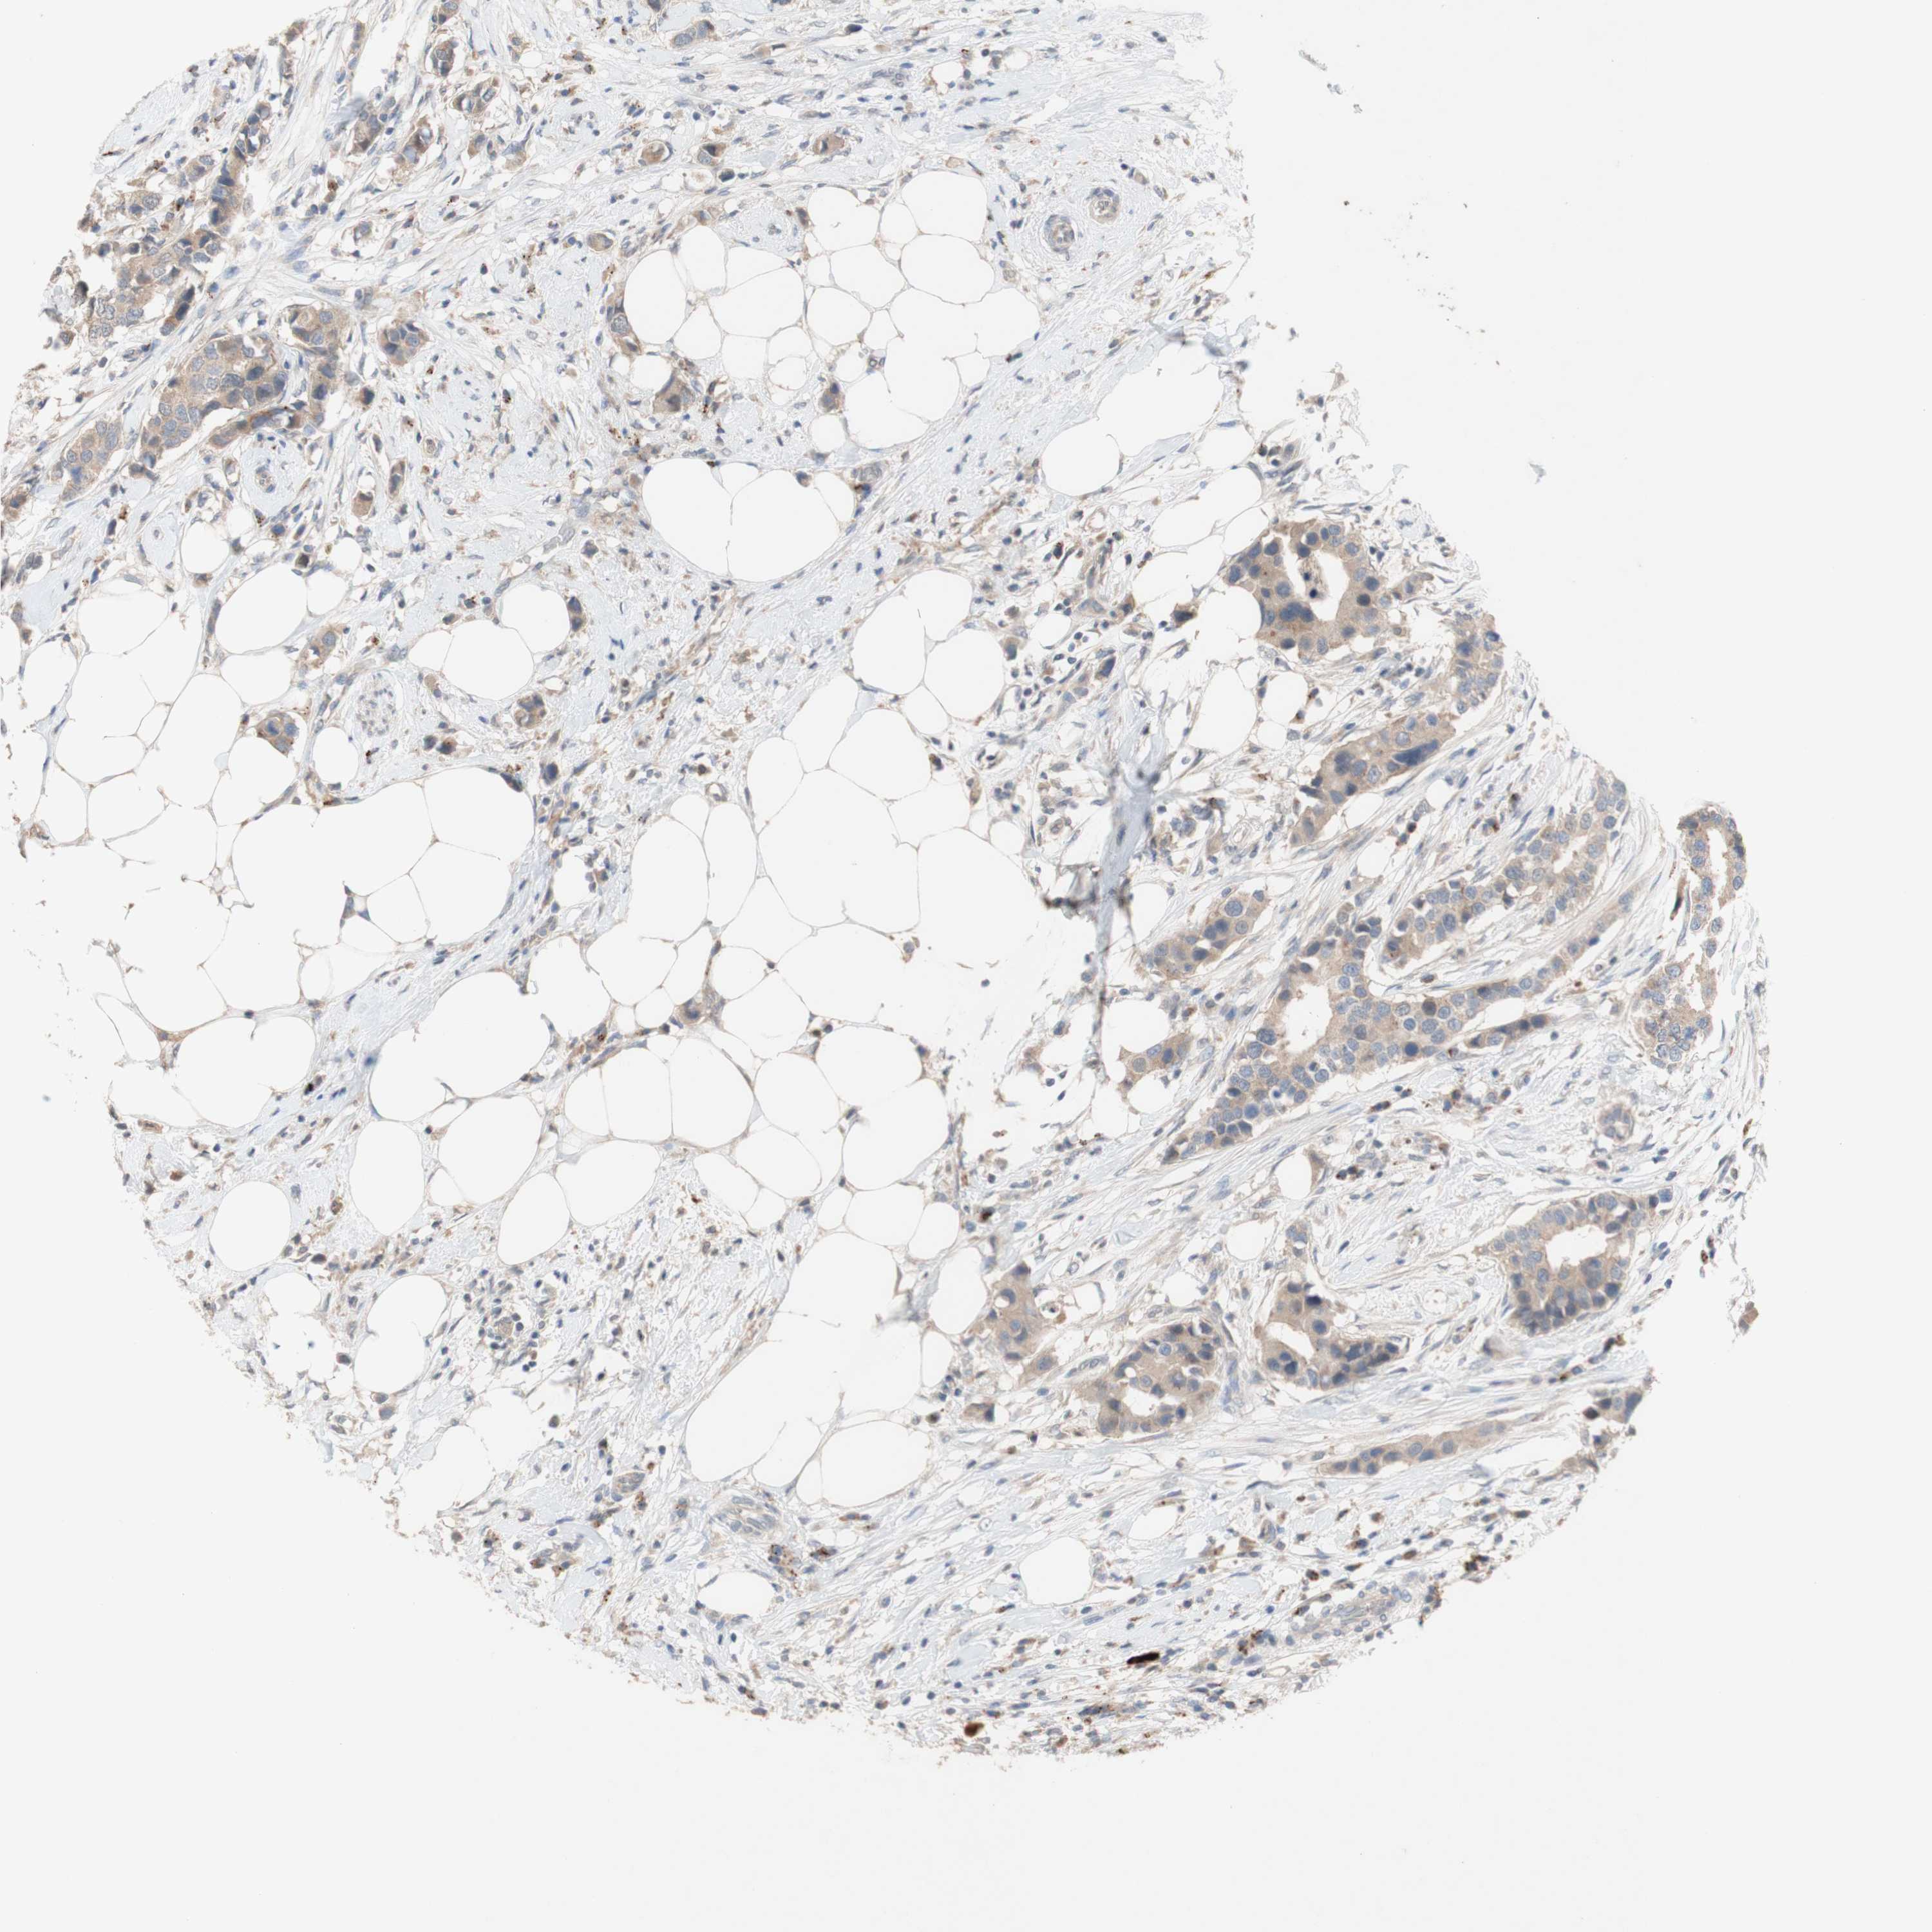

CANCER BREAST CANCER Show tissue menu

BRCA TCGA BRCA VALIDATION PROTEIN EXPRESSION